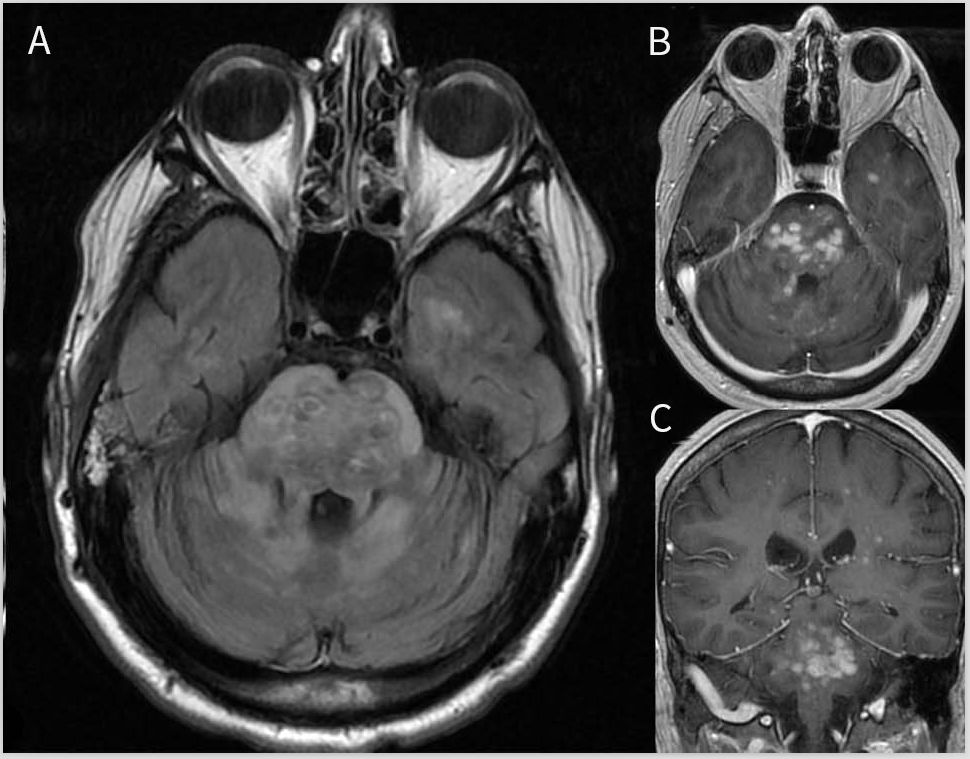

MRI可表现表为脑膜、下丘脑-漏斗状和颅神经等受累,或脑积水、实质和硬脑膜占位病变(图5)。颅底或广泛的软脑膜增强是NS的特征性表现。增强模式可为弥漫性、结节状或沿血管周围空间扩散。NS脑干病灶的形态为非特异性,如果存在实质病灶时可出现增强,并常伴软脑膜强化。这种典型的“由外而内”的外观强烈支持NS。硬脑膜的不连续增强和T2低信号认为是区分位于后颅窝轴外肉芽肿样占位与脑膜瘤等肿瘤的特征。尽管颅底周围血管存在炎症,但脑干梗死还是罕见。当脑干改变与纵向广泛性脊髓炎同时发生,脊柱背侧强化提示NS。CSF蛋白水平中度升高(> 1g/L),且通常无寡克隆带可能有助于NS与MS的鉴别诊断。CSF血管紧张素-转化酶(ACE)的水平既不特异也不敏感。

图5 神经结节病患者的MRI影像。轴位T2加权显示中脑外侧(A)和脑桥(B)存在病灶(箭头),病灶伴结节样增强(C,D)。冠状位T1增强图像(E)显示进一步的病灶增强,延伸至大脑脚下外侧缘。矢状位T1增强图像(F)显示颈、延髓增强病灶(箭头),颈髓多发病灶表现为“由外而内”的增强模式(宽箭头)。轴位T1增强图像(G,H)显示多发硬膜外脑干、小脑和颅底增强病灶(宽箭头),延髓增强病灶(宽箭头)和基底脑膜增强(长箭头)。